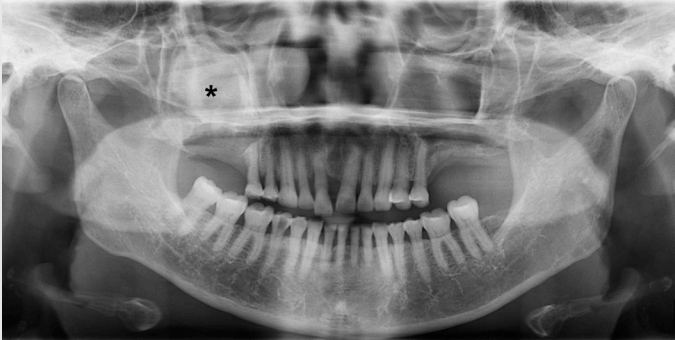

이 증례보고는 조선대학교치과병원 기관생명윤리위원회에서 승인 번호 CUDHIRB 2401 003으로 승인을 받았다. 72세의 여자 환자가 1년 전 우측 상악 제1,2 대구치 발거 후, 수개월 동안 지속해서 해당 부위에서 염증 삼출물이 나온다는 증상을 호소로 조선대학교 치과병원에 내원하였다. 처음 내원했을 때, 양측 상악 제1, 2대구치(#16,17,26,27)는 결손된 상태였고 임상 검사에서 발치 후 치유가 완전하게 진행된 정상 구강 점막의 형태를 관찰할 수 있었다. 환자는 전신 질환으로 고혈압과 당뇨가 있었으며, 안면부 외상이나 상악동 수술 등의 병력은 존재하지 않았다.파노라마방사선영상에서 우측 상악동 내부 대부분의 공간이 방사선불투과상으로 채워져 있는 것을 관찰할 수 있었다(Fig. 1). 또한 반대측과 비교하였을 때 우측 상악동 저의 경계가 분명하지 않고 치조골의 골밀도가 감소된 소견을 보였다. 추가적인 평가를 위해 cone-beam computed tomography(CBCT)에서 얻어진 영상을 axial, coronal, panoramic plane으로 재구성하였다. 재구성된 영상에서 우측 상악동 내부를 채우고 있는 장경 3.5 cm정도의 낭종 병소가 관찰되었으며, 상악동의 전방 및 후외측 골이 팽융되고 상악동의 후외측 경계와 상악 치조골이 병소에 의해 소실된 소견이었다(Fig. 2). 병소의 경계는 대체적으로 잘 구분되고 타원 형태의 구조를 보였다. 경계 부위에서는 비후된 형태의 경화성 골 변연이 관찰되었고 병소 내부에서는 불규칙하고 무정형의 석회화가 산재되어 있었다. 술후상악낭(postoperative maxillary cyst)과 석회화치성낭(calcifying odontogenic cyst)을 감별진단으로 고려하였다.본원 구강악안면외과에서 전신마취 하 구강 내 치조정측 접근을 통한 수술적 적출을 시행하였는데, 수술하면서 우측 상악동에서 농이 배출되는 양상과 육안상으로 볼 때 육아종처럼 보여지는 종괴(granulative mass)를 관찰할 수 있었다(Fig. 3). 수술 후 병리조직학적 검사 결과, 광범위한 골화를 동반한 콜레스테롤 육아종(cholesterol granuloma with massive ossification)으로 진단되었다(Fig. 4).환자는 수술 후 약 2주 정도 수술 부위에 대한 관리와 상악동의 배농 및 환기 상태의 유지를 위해 추가적인 처치를 받은 후 퇴원하였고, 수술 8개월 후 시행한 CBCT 검사에서 재발과 관련된 소견이 관찰되지 않았으며(Fig. 5) 현재까지 별다른 합병증 없이 추적 관찰 중이다.

Figure 1.

There is a haziness in the right maxillary sinus (*) with bony bulging at the posterior margin of the sinus and the bone density of the upper right alveolar bone is also reduced.